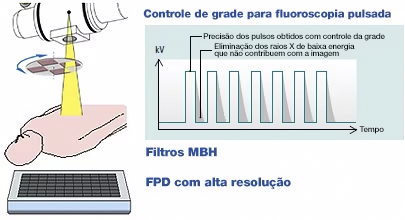

- Controle de grade na fluoroscopia pulsada, reduzindo a dose sem comprometer a qualidade.

- Filtros Multi Beam Hardening (MBH), minimizando artefatos e exposição desnecessária.

- Pixel ultrapequeno de 139μm, melhorando a nitidez das imagens.